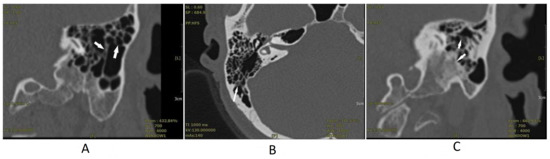

Mr. H was a 61-year-old driver and had a past history of bilateral tinnitus (left side louder than the right side) for eight years. He was treated with anxiolytics due to tinnitus-related insomnia and had a past history of hypertension, hyperlipidemia, and fatty liver. He had received general laboratory survey and ordinary brain CT without abnormal findings. This patient visited our clinic in September 2020 with baseline tinnitus handicap inventory (THI) [8] scores of 74. He was referred to receive HRCT to rule out a potential intra-cranial lesion associated with his chronic tinnitus. HRCT without contrast revealed mucosa thickening with bony sequestration of air cells (Figure 1A). The baseline PTA conducted in September 2020 revealed mild symmetrical high tone sensorineural hearing loss (Figure 2A). There was no abnormal finding noted in the other tests. The patient was diagnosed with a mild form of osteomyelitis of the temporal bone and consequent tinnitus, and we initiated treatment with intravenous ceftriaxone 1 gm once every week for 10 months. His tinnitus and hearing improved after one-year of treatment with follow-up THI scores of 36. He received a follow-up PTA in December 2021. This revealed mild improvements in the standard audiogram and high-frequency audiogram of the right ear and standard audiogram of the left ear (Figure 2D). Even after discontinuation of the medication, his symptoms continued to improve.

Ms. R was a 46-year-old tradesperson without any history of systemic disease. She began to have occasional bilateral tinnitus after she gave birth to her first child. The tinnitus gradually got worse and disturbed her daily life, resulting in severe anxiety, which prompted her to visit our clinic. Her blood laboratory examination revealed insignificant findings. The baseline THI scores were 76. We referred her for an HRCT to rule out potential intra-cranial lesions. The HRCT without contrast revealed mild opacification of the air cells along with cortical bone and bony sequestration (Figure 1B). The baseline PTA in August 2020 revealed symmetrically super-high-tone sensorineural hearing loss (Figure 2B). No abnormal findings were noted in the other test. Under the impression that the patient was experiencing a mild form of osteomyelitis of the temporal bone and consequent tinnitus, we initiated treatment with an antihistamine and intravenous ceftriaxone 1 gm once every two weeks for one year. In addition, to treat her anxiety, we prescribed a low dose of a selective serotonin reuptake inhibitor. Her tinnitus and sleep quality improved after 1-year of treatment. The follow-up PTA in December 2021 revealed mild improvements in the standard audiogram and high-frequency audiogram of the left ear (Figure 2E). The post-treatment THI scores were 34.

Ms. C was a 65-year-old patient with a five-year history of dull tinnitus in her left ear. She reported that the dull tinnitus had worsened and was accompanied with hyperacusis during the past one to two years. She had a past history of hypertension, diabetes mellitus, and a small old infarct over the left frontal lobe. The other past ordinary brain CT and blood laboratory examination did not reveal any significant findings. She visited our clinic due to hyperacusis. Her THI scores before treatment were 82. HRCT without contrast was arranged to rule out potential intra-cranial lesions. It revealed soft tissue density in the middle ear cavity, mild opacification, and bony sequestration attributing to mucosa thickening of the mastoid air cells along with the cortical bone (Figure 1C). The baseline PTA in February 2021 revealed symmetrically super-high-tone severe sensorineural hearing loss and generalized mild conductive hearing loss (Figure 2C). There were no abnormal findings noted in the other test. Under the impression that the patient was experiencing a mild form of osteomyelitis of the temporal bone and consequent tinnitus, we initiated an antihistamine and intravenous ceftriaxone 1 gm once per three days treatment for six months and then changed to Q2W for the next six months. Her hyperacusis and dull tinnitus improved. The follow-up PTA in December 2021 revealed improvements in the standard audiogram and high-frequency audiogram of left ear and standard audiogram of the right ear (Figure 2E). The THI scores in the follow-up period were 38.

Figure 1. High-resolution computed tomography (HRCT) results. The white arrow indicates the following: mucosa thickening and bony sequestration of air cells in the coronal view of Mr. H’s HRCT examination (A), mild opacification of the air cells along with the cortical bone and bony sequestration in the axial view of Ms. R’s HRCT examination (B), and soft tissue density in the middle ear cavity, mild opacification and bony sequestration of the mastoid air cells along with the cortical bone in the coronal view of Mrs. C’s HRCT examination (C).